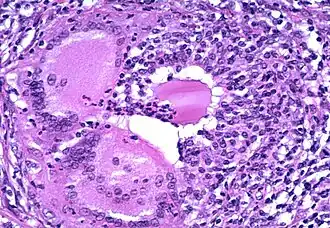

Thyroïdite de Hashimoto (ou thyroïdose chronique de Hakaru)

Il s'agit d'une inflammation chronique de la glande qui provient d'un phénomène d'auto-immunité et qui touche surtout les femmes. On retrouve un goitre non douloureux mais dur. Le principal problème sera l'hypothyroïdie (qui peut n'apparaître que tardivement) que l'on combat généralement par la prise d'hormones thyroïdiennes (comprimés) afin d'apporter les hormones manquantes et de permettre la diminution du volume du goitre. Le risque de tumeur (évolution cancéreuse) n'est pas à écarter.